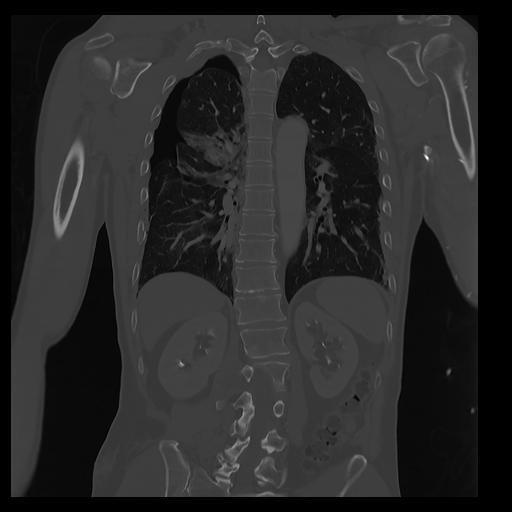

32 PULMON,CE,Coronal,3.000,PULMON,Coronal,